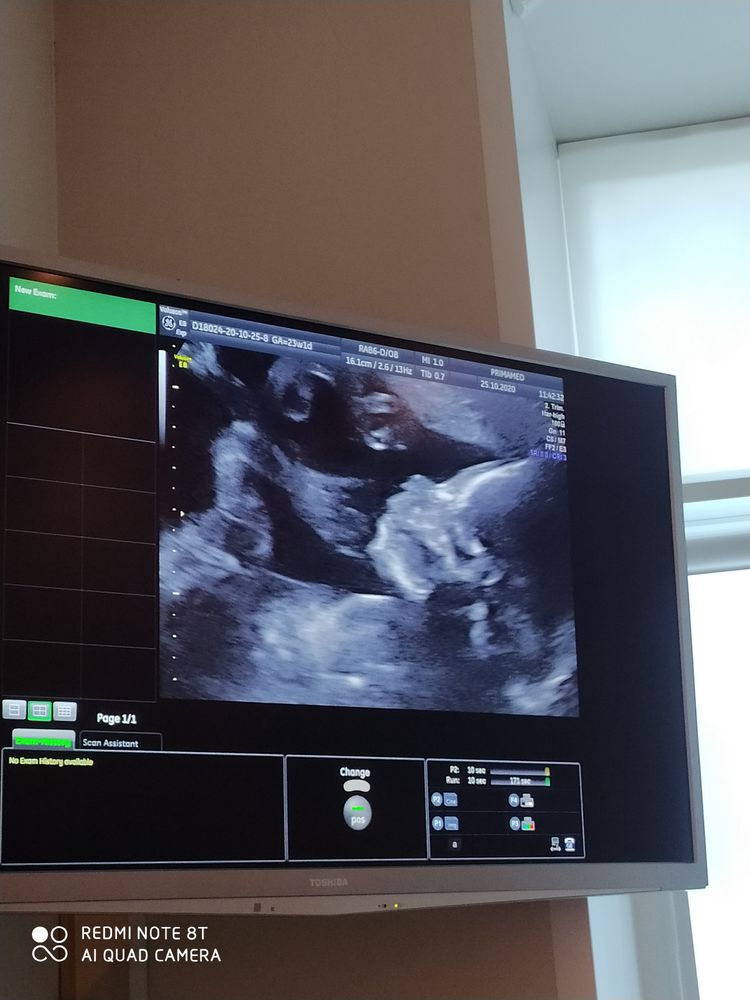

23 недели полет нормальный))

25.10.2020